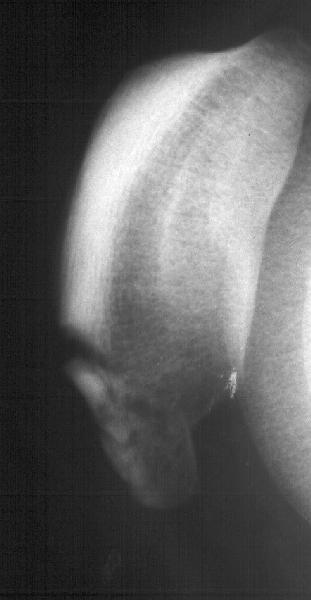

Мужчина 33 лет поступил через 2 недели после автоаварии (был за рулем) с переломом бедра. На этой же стороне есть перелом нижнего полюса надколенника. Клинически отека и гемартроза нет, интенсивная пальпация слабо болезненна прямо над линией перелома. Пальпаторно разгибательный аппарат сохранен. Бедро вчера синтезировано стержнем. Сделал сразу после этого снимок в полном сгибании - ничего никуда не расходится, и у меня рука не поднялась. Есть ли настоятельная необходимость оперативной фиксации, и если да, то чем?

Остеосинтез бедра был 20.08.02, сегодня, 23.08.02, пациент пошел домой с одним костылем. Безболезненно сгибает колено до прямого угла (при

попытке согнуть дальше болит не колено, а передняя группа мышц в середине бедра), лежа свободно поднимает и удерживает на весу прямую

ногу. Со сгибанием до острого угла решили недели 2-3 подождать, и все.